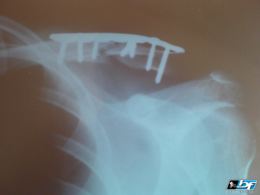

Rameno po pádu

IWY

1